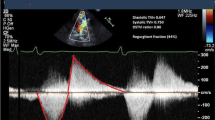

Doppler echocardiographic parameters. a PHT derived from CW Doppler echocardiography tracings. The deceleration slope of the PR (red line) represents the PHT. The PHT in this example is 118 ms, which suggests mild PR. b PRi measured with CW Doppler echocardiography. PRi is defined as the ratio of the duration of the regurgitation flow represented by line 2 (in this example 433 ms) divided by the total diastolic time, line 1 (in this example 646 ms). c The ratio of regurgitation jet width at the level of the PV (straight line) to PV annulus width (dashed line) measured during early diastole obtained by color-flow Doppler echocardiography. d DSTVI measured from the main pulmonary artery PW Doppler spectral tracing (red lines), is the area surface of the diastolic regurgitation flow (i.e. surface area 2) divided by the area surface of the systolic flow (i.e. surface area 1)

The jet diameter was measured during early diastole using Color Doppler while avoiding aliasing by adjusting the Nyquist limit (Fig. 1c). The annulus diameter was measured in the same view using 2D images without color. Both measurements were used to calculate the jet/annulus ratio [24]. Regarding jet/annulus ratio, the optimal threshold for identifying significant PR has been reported, but inconsistently [13,14,15,16,17].

The pulsed-wave (PW) Doppler tracing from the main pulmonary artery was used to obtain the velocity–time integrals of diastolic and systolic pulsed-waves (Fig. 1d). The diastolic to systolic time velocity integral (DSTVI) was calculated by dividing the surface area of the diastolic flow curve by the surface area of the systolic flow curve. Mercer-Rosa et al. defined a DSTVI > 0.49 as the cut-off between mild and hemodynamically significant PR [15]. The optimal threshold for the identification of significant PR for all 4 Doppler echocardiographic measurements were re-assessed.